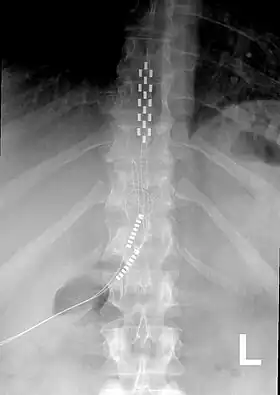

Anterior view X-ray of a spinal cord stimulator (SCS) implanted in the thoracic spine |